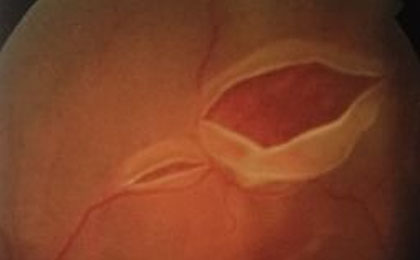

揉眼睛也会视网膜脱离 导致视网膜脱落的原因有哪些??干净流眼泪大部分的人都是用手来揉一揉,殊不知视网膜脱离也是比较麻烦的。

积极识别黄斑病变症状 了解科学的治疗方式。下面让我们来了解一下黄斑病变有哪些症状?以及应该如何治疗,这样才能更好的恢复眼睛上的视力。